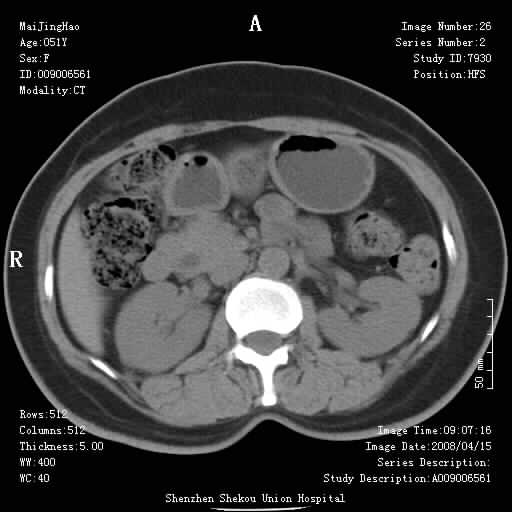

以下是引用余辉在2008-4-26 8:55:00的发言:[br]患者有结石史,此次腹痛4小时,胆总管全程扩张,应有胆总管末端梗阻,此次仍考虑胆结石症,积气不外两种原因,一种是结石下移时肠道内气体逸入,其次为产气菌感染。(倒数第三幅图像于扩张之胆总管末端似可见稍高密度影,考虑为结石影)

以下是引用听蝉观竹在2008-4-26 11:41:00的发言:[br]胆道手术分两种情况:[br]1、如果仅仅做胆囊切除手术,肝内胆管不会积气,只会出现胆总管代偿扩张,因为奥迪氏括约肌依然功能正常胆道与外界并不相通;[br][br]2、胆囊切除+胆总管空肠吻合手术(即roux-y式),则肝内胆管会出现积气,只是因为胆管与小肠相通,气体来源于小肠。这是临床十分常见的手术。[br][br]这个病例应该是胆囊切除+胆总管空肠吻合手术,是正常手术后表现,并不是胆道感染的表现。

以下是引用听蝉观竹在2008-4-27 10:10:00的发言:[br]关于胰头大小问题有几种测量方法和正常值:[br][br]1、直量法:横径<4cm;[br]2、胰头横径与相邻层面椎体横径的比值为二分之一,超过椎体横径就提示胰头增大;[br]3、正常组成年人肠系膜上动、静脉水平夹角正常值范围为4.9°~34.7°大于35°提示胰头增大。[br][br]上述方法只是一种具体的判断,是“量”的评估,更重要的是“质”的评估:一是观察边缘是否光滑,有无局部隆起,有无分叶;二是观察密度(增强,尤其在动脉期和门脉期)是否均匀。[br][br]所以对于胰头是否有异常不仅仅是是目测可以解决问题的,不要轻易就说“胰头增大”。还有一个问题就是测量胰头应该在增强ct上进行,这样可以避免将血管测量进去。[br][br]为什么啰嗦讲怎么多,因为我们实际工作中同样存在影像科医生和临床医生动不动就说胰头增大,说是胰头癌。大家看看是不是这种情况?[br][br] 我个人观点-----本病例的胰头不增大。[br][br][本贴已被 听蝉观竹 于 2008-4-27 10:12:41 修改过]